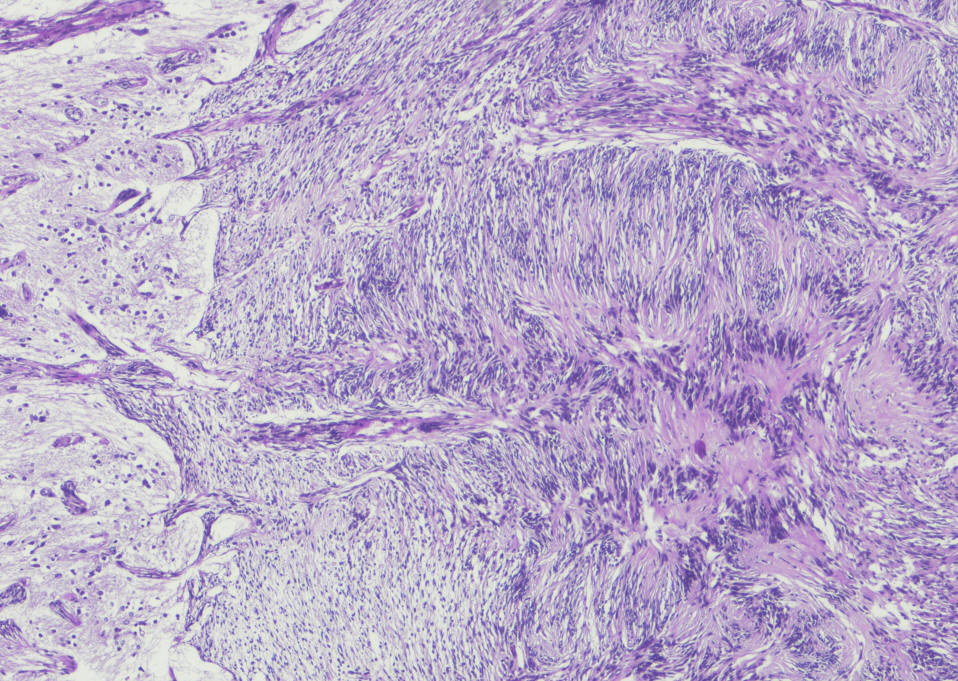

Sections show a circumscribed tumor composed of spindle cells displaying prominent nuclear palisading and Vercoy bodies. This lesion exhibits peripheral tongues extending into the brain cortical tissue. There is no evidence of mitotic activity, nuclear anaplasia or necrosis. Tumor shows heavy interstitial reticulin deposition and reacted positively to S-100 and Vimentin. Tumor did not react to GFAP and EMA. Proliferative index was estimated at 2%, but not exceed 3% in any area. There is no evidence of malignancy. Conclusion: Intracerbral schwannoma. ( Prof. Yahya F. Dajani Consultant pathologist. 29-January-2022.